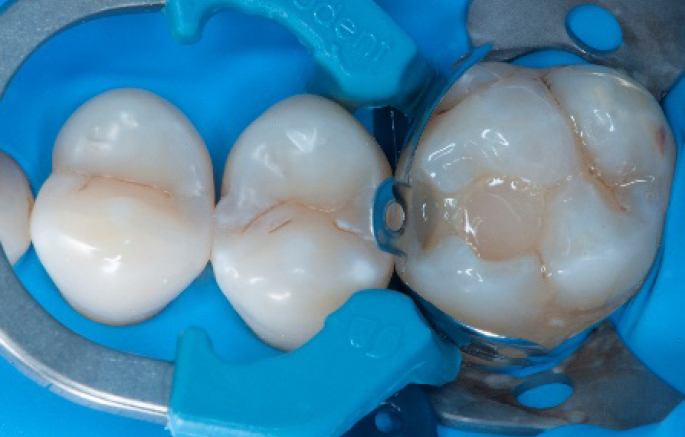

Step 4:

The complete Palodent1 system in place: sectional matrix, wedge and ring.

Step 5:

Buccal view of the Palodent1 system.